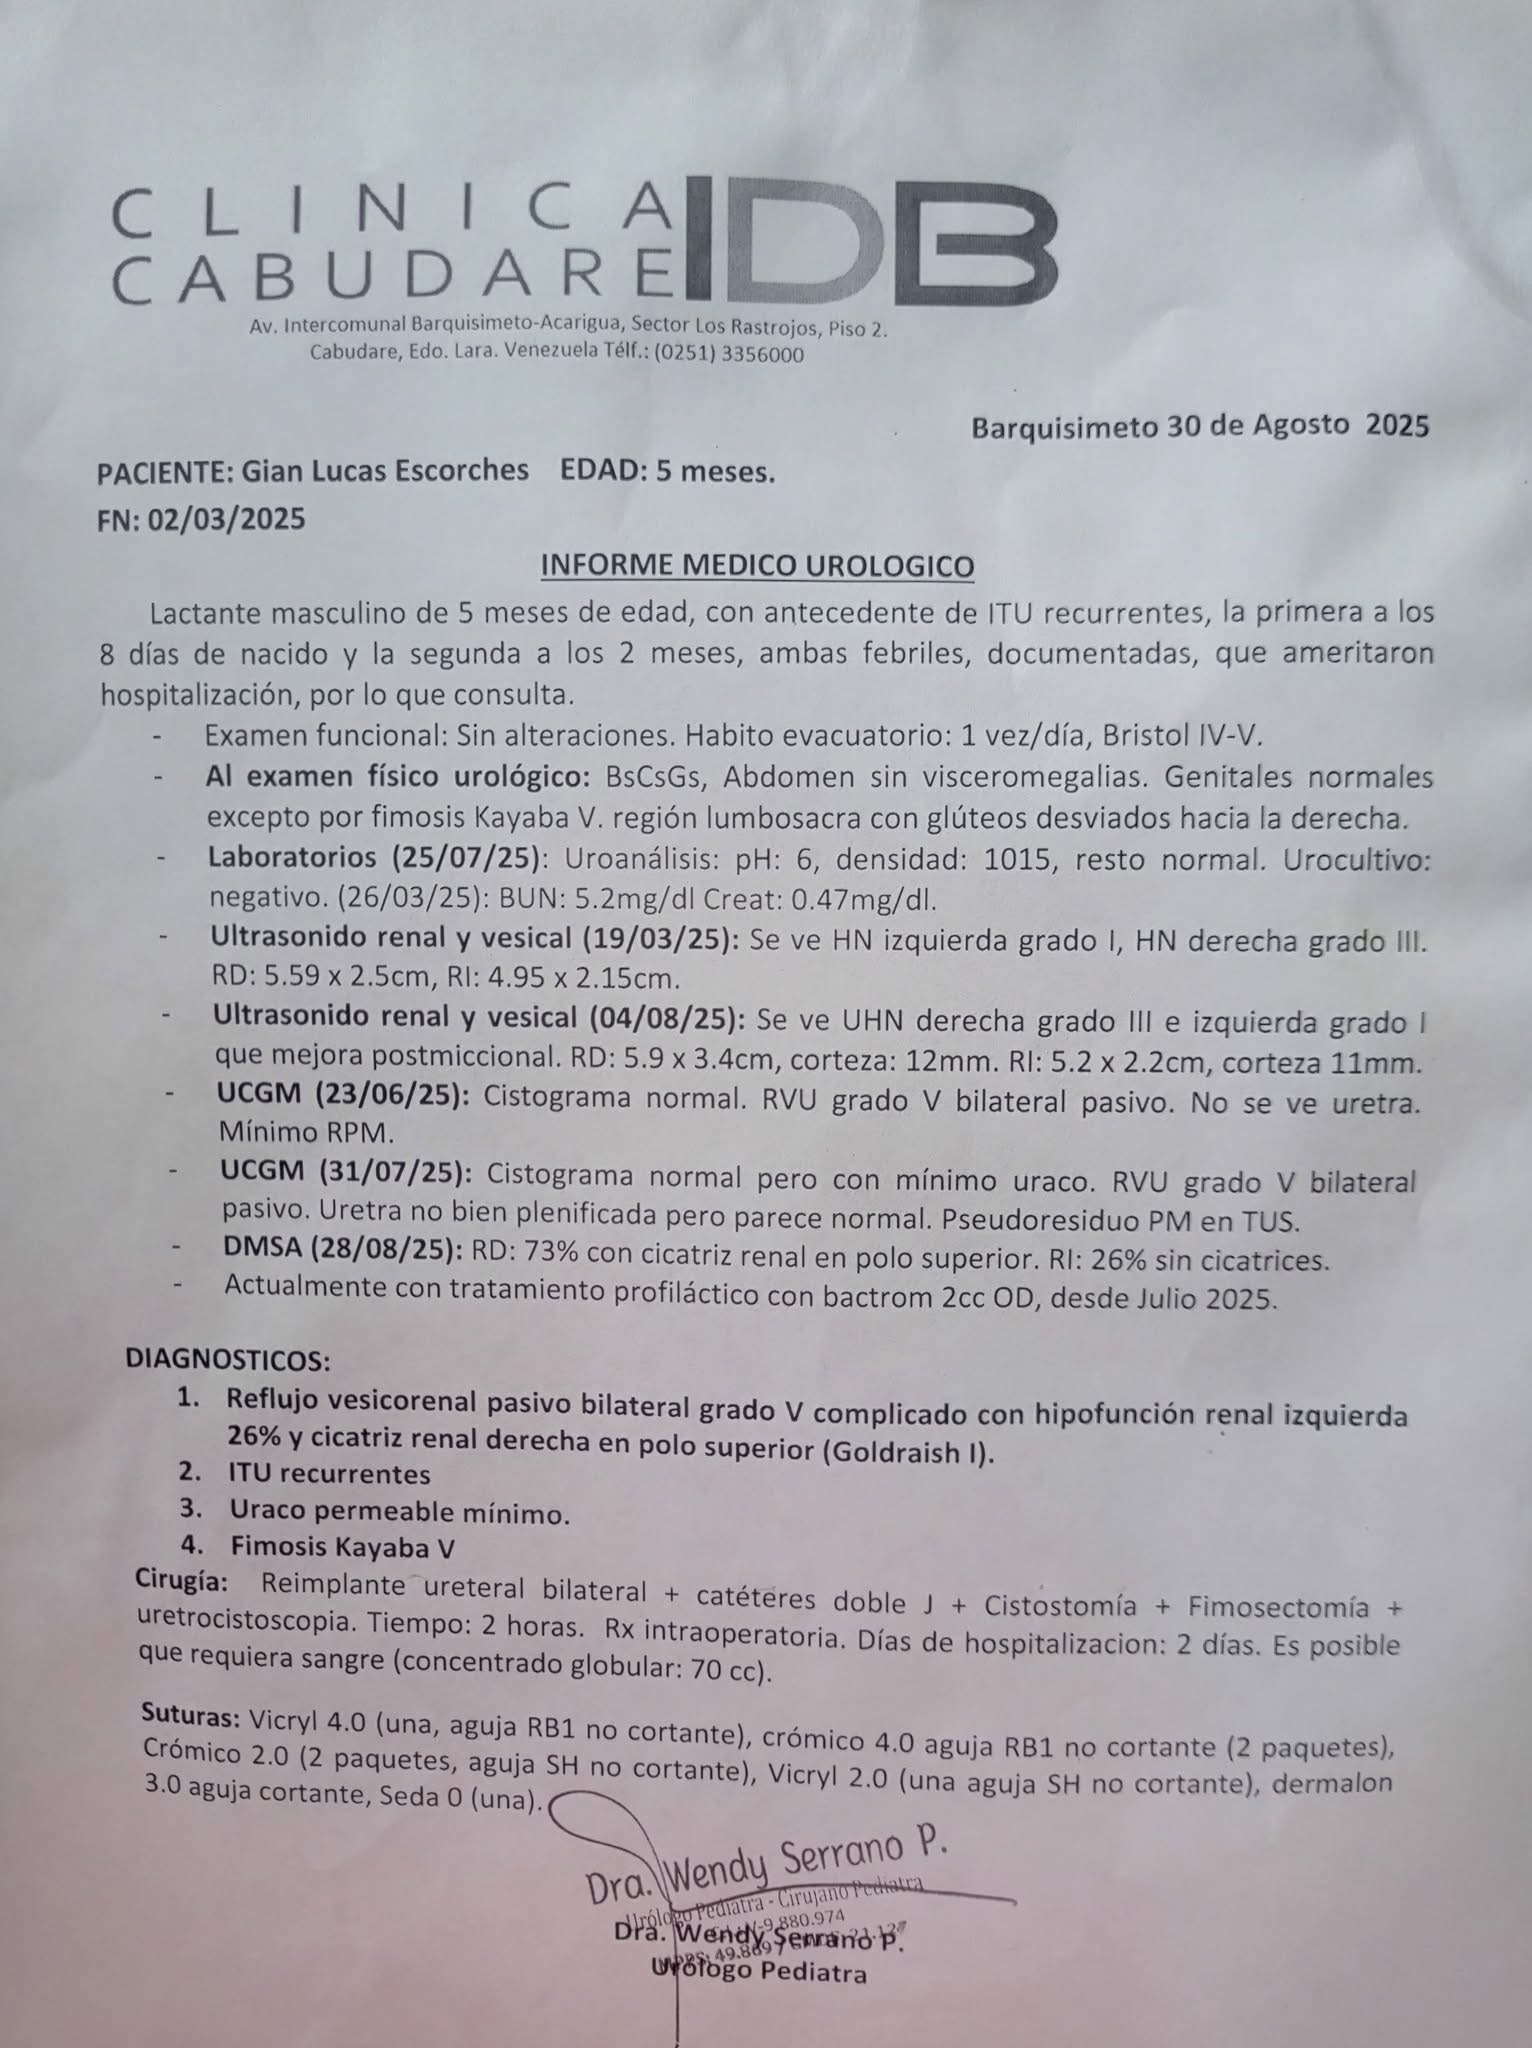

Seguimos en esta lucha y en esta causa hasta lograrlo, poco a poco hemos sumando para que se haga posible todo, gracias a cada personita quea sumado su gran esfuerzo y granito de arena para ir recaudando y poder completar para ser operado, Dios está obrando muy bien en mi vida, así que sigo en pro de ayuda y ahí explico el costo de mi operación, ayúdame compartiendo y difundiendo, ya quiero ser un niño completamente feliz y sano